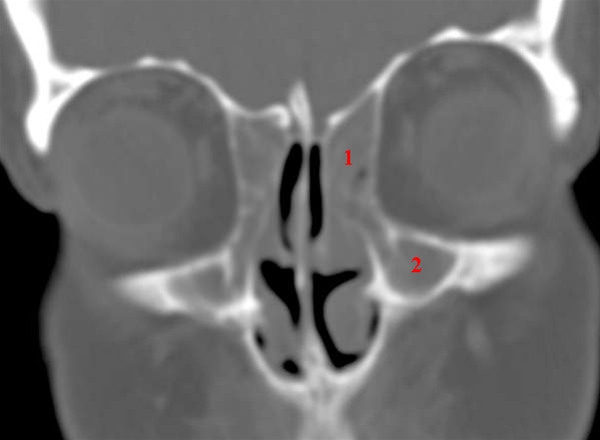

CT-skanning, coronal.

Slørede ethmoidalceller (1) og sinus maxillaris (2) på begge sider.